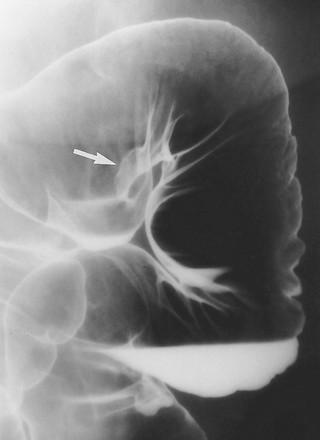

3.1.1. Tổn thương hình polyp

Các polyp lồi từ niêm mạc tạo hình khuyết trong vũng baryt hoặc có viền trắng do baryt phủ và khí – thấu tia x quang bao quanh khi chụp đối quang kép. Các polyp có thể có cuống (Hình 3) hoặc không. Khi nhìn chếch, các polyp có hình “mũ quả dưa”-“bowler hat”(Hình 4).

Hình 3. Polyp có cuống. Chụp cản quang kép bộc lộ một polyp có cuống dài với đầu hình củ hành (mũi tên thẳng) mọc từ niêm mạc (mũi tên cong) đại tràng xuống.